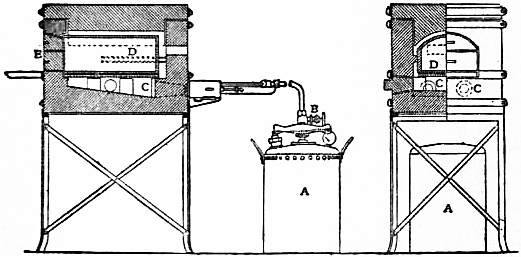

Laser Assisted Endoscopic Stapedectomy A Prospective Study Poe 2000 The Laryngoscope Wiley Online Library

Https Onlinelibrary Wiley Com Doi Pdf 10 1097 00005537 200005001 00001

Laser Assisted Endoscopic Stapedectomy A Prospective Study Poe 2000 The Laryngoscope Wiley Online Library

Laser Assisted Endoscopic Stapedectomy A Prospective Study Poe 2000 The Laryngoscope Wiley Online Library

Laser Assisted Endoscopic Stapedectomy A Prospective Study Poe 2000 The Laryngoscope Wiley Online Library

Laser Assisted Endoscopic Stapedectomy A Prospective Study Poe 2000 The Laryngoscope Wiley Online Library

Https Onlinelibrary Wiley Com Doi Pdf 10 1097 00005537 200005001 00001

Laser Assisted Endoscopic Stapedectomy A Prospective Study Poe 2000 The Laryngoscope Wiley Online Library